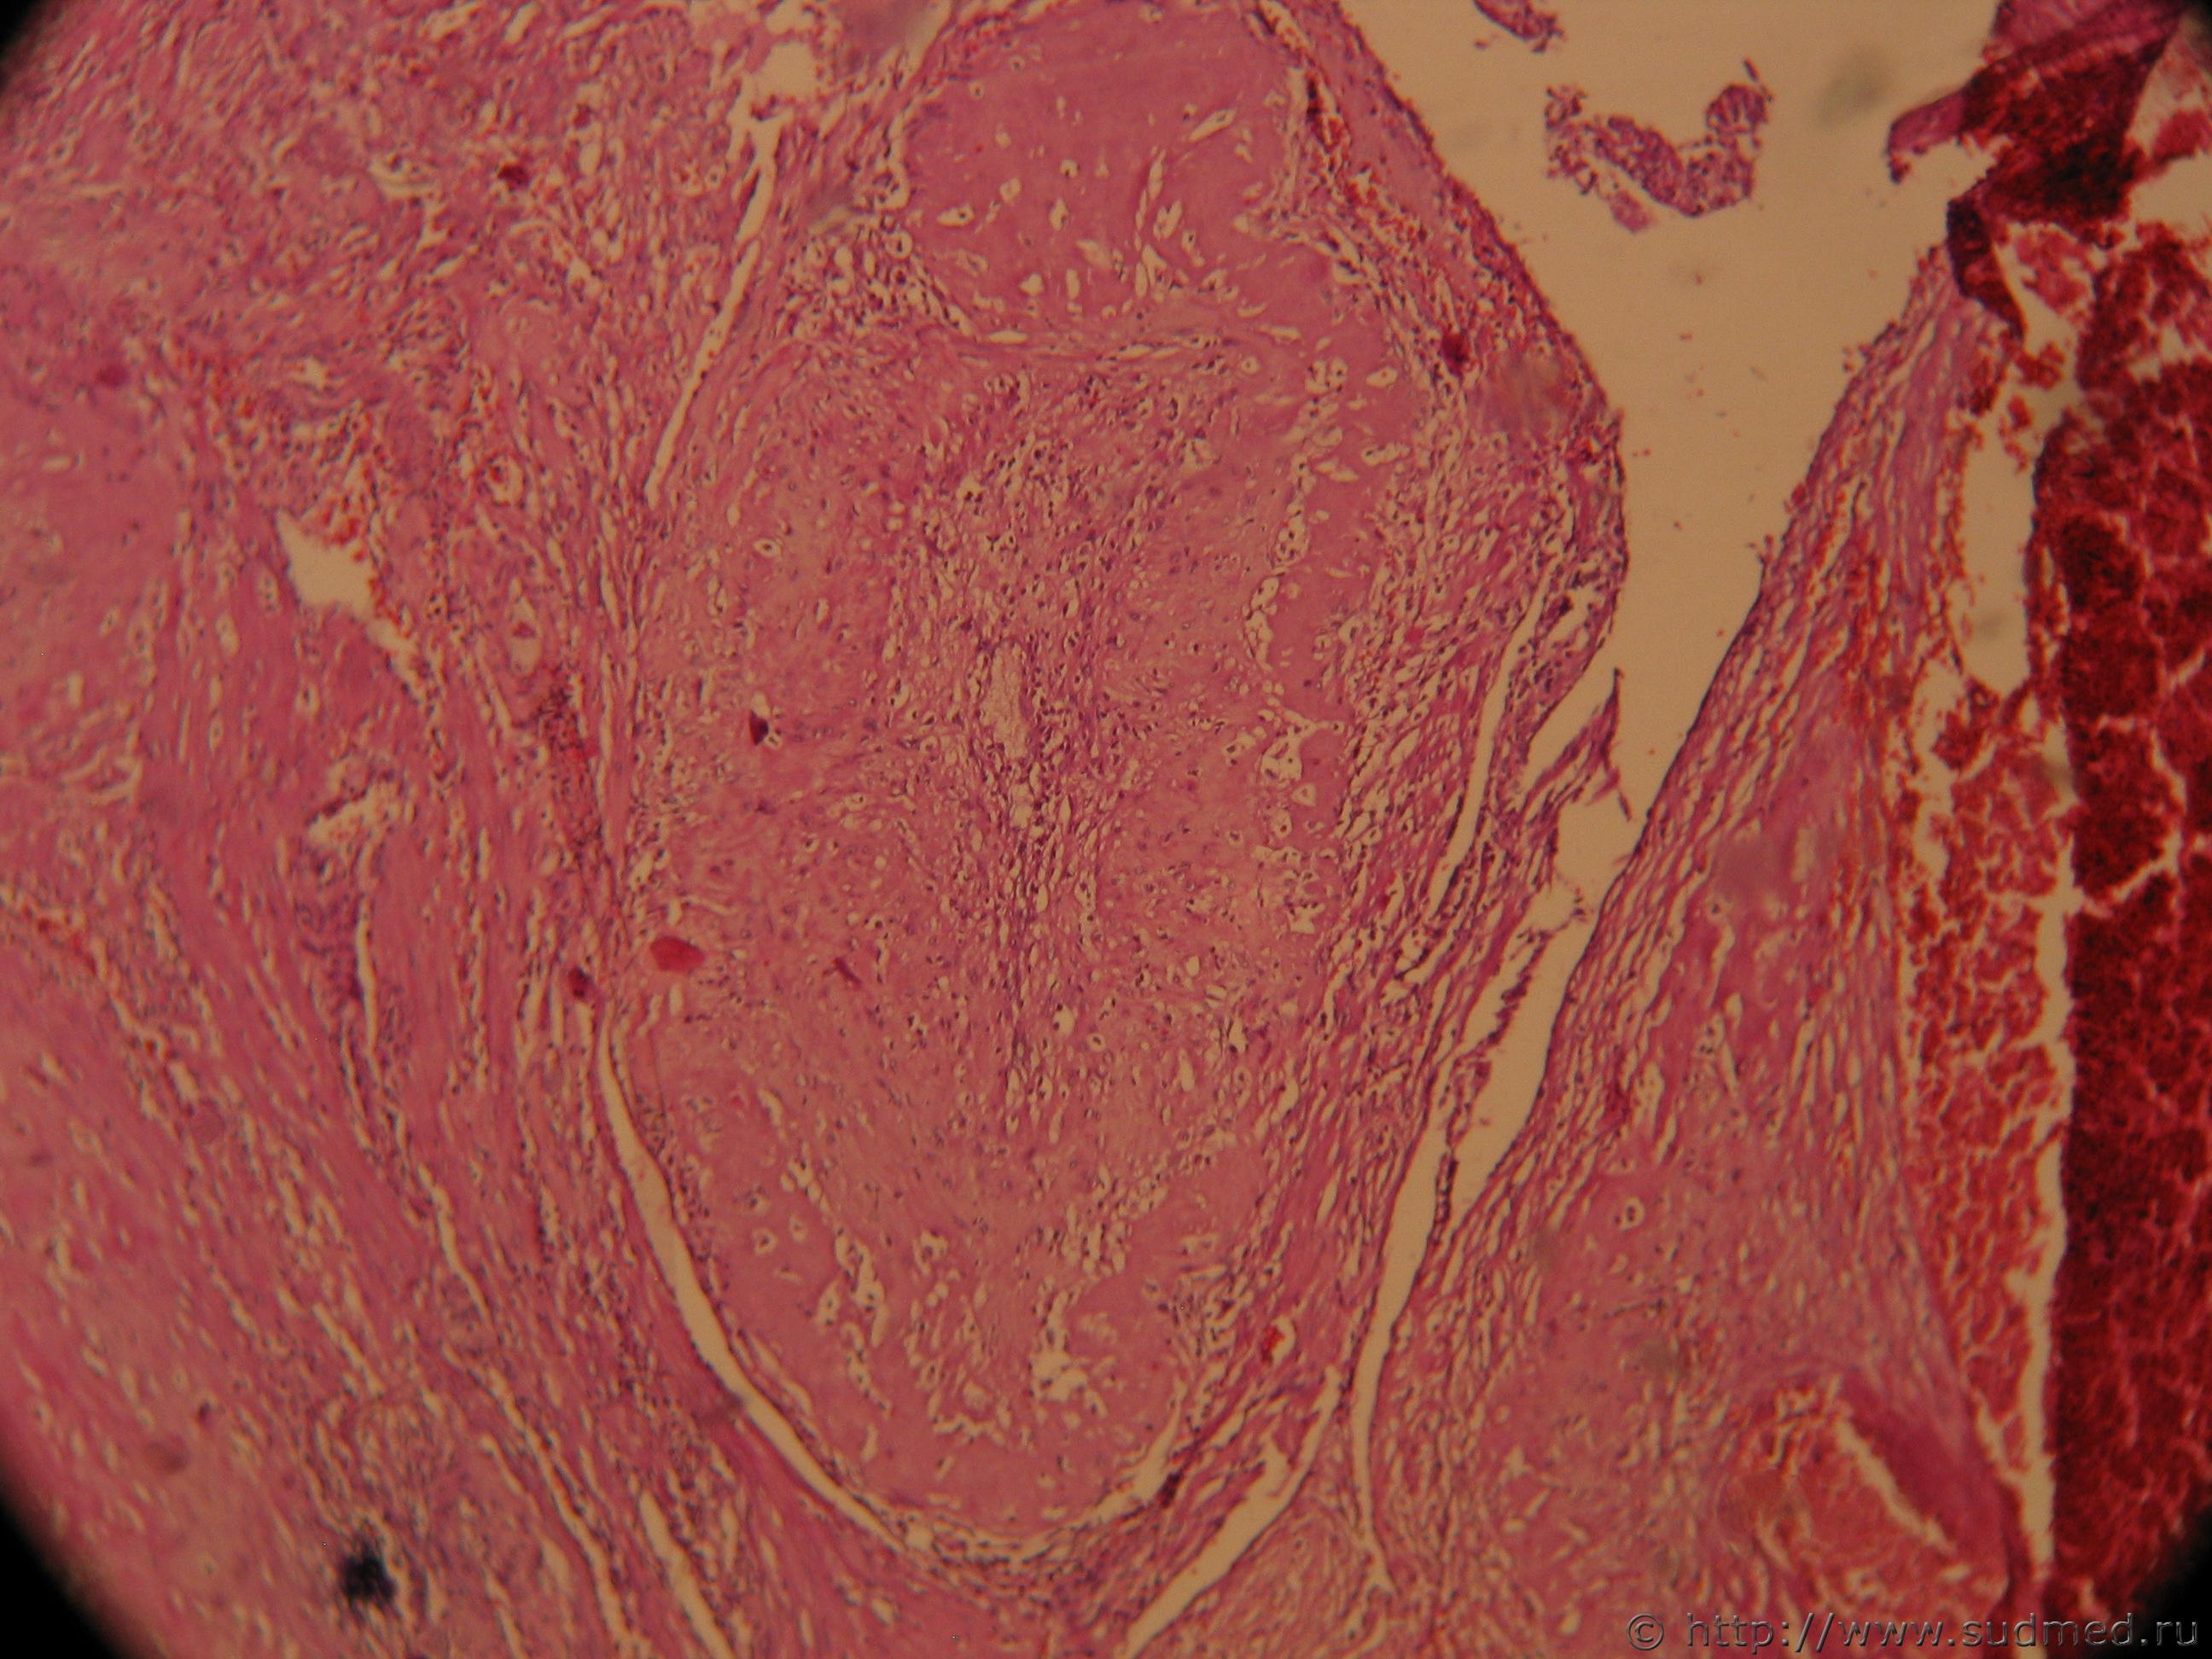

Как-то была тема в КЦ "Плацентарный полип после родов". Недавно попался случай: экстирпация матки в связи с маточным кровотечением на 16 сутки после кесарева. Исследовали патанатомы, я только стекла пересметриваю. Макроописание:"Матка 12Х10Х6 см полость м-ки вскрыта, расширена, по задней стенке эндометрий представлен рыхлыми темно-серыми полипососочковыми разрастаниями, миометрий местами толщиной 2,5 см (***) структуры с очаговыми кровоизлияниями. Микроописание с ним я немного несогласен. Вот фото, если понадобится еще сделаю.

Фото 1: Вместо эндометрия некрозы, крововизлияния, тромбоз сосудов, кое-где с некрозом сосудистых стенок, лейкоцитарные инфильтраты и гиалинизированные ворсины хориона.Судебная медицина - Прикрепленное изображение

Вот, что по моим представлениям ворсины зрелой плаценты Судебная медицина - Прикрепленное изображение

Ув.Х400 Эта группа клеток на самой первой фотографии (начало топика) на 9 часов при ув.Х40

уважаемые коллеги! микрофото не четкие, но я хотел добавить о том, что не отделившийся участки плацентарной ткани взависимости от объема, как остатки плацентарной ткани поэтапно превращается в полипозную ткань, если меньше размером. До 16 дней кровотечение следовало бы ожидать, в результате фибриноидного некроза стенки сосудов стволовых, промежуточных ворсин и самых ворсин в целом с воспалительным ответом в виде лейкоцитарной реакции и тромбозом сосудов эндометрия. На микрофото не видно миометрии. Видны плацентарная ткань с фибриноидным некрозом , очаги кровоизлияния с тромбозом сосудов умеренной лейкоцитарной реакцией. В данной ситуации нужно отдифференцировать истинное приращения от остатков неотделившихся участков плаценты, если в миометрии имелись трофобластные клетки с синцитиями и от трофобластной болезни, эти три патологии имеют три разных этиопатогенеза. Мой предварительный ответ по представленным двум микрофото- плацентарный полип , развившегося в результате неполного отделения плаценты.